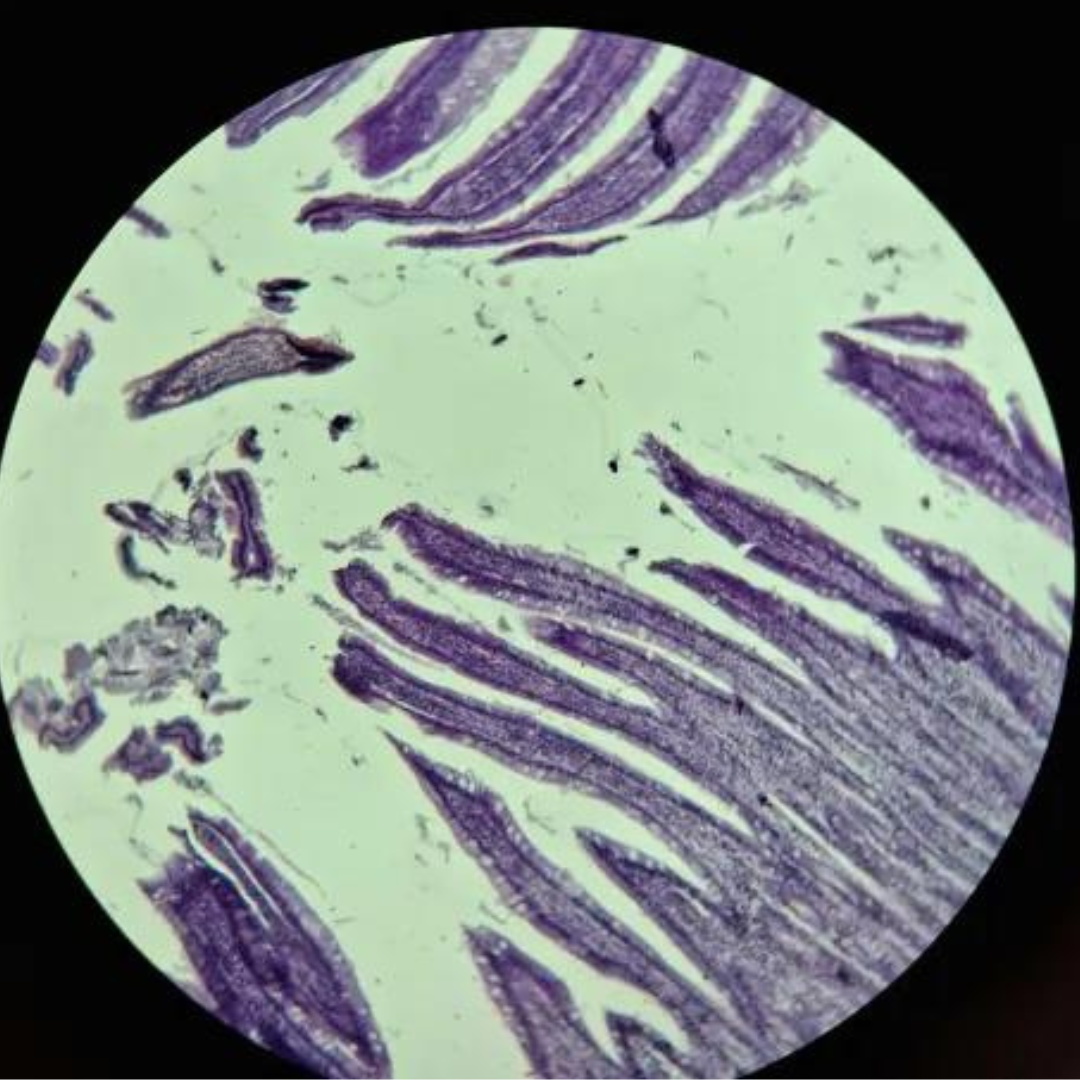

Bone

Bone

Bone

Bone

Bone